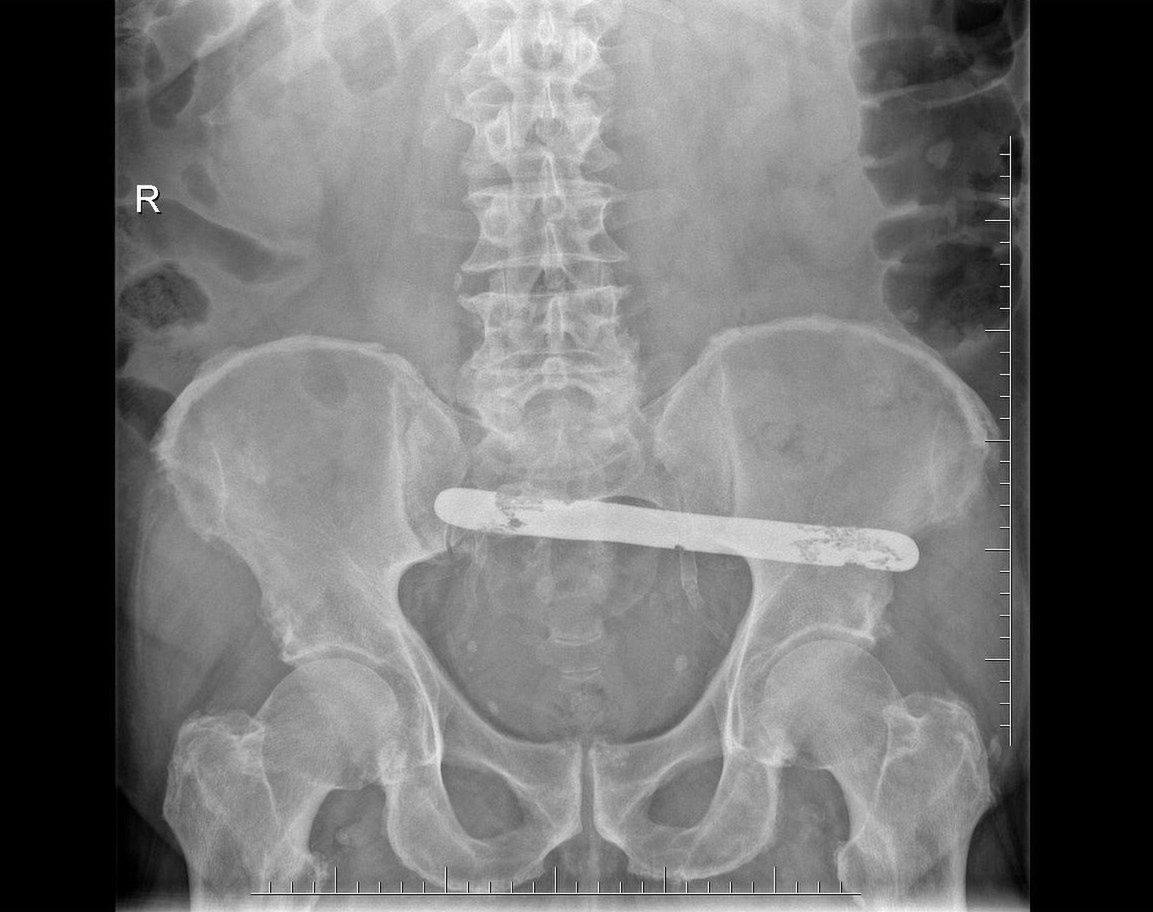

Pan Janusz trafił wkrótce do szpitala onkologicznego w Warszawie. Jak się okazało, ból nogi i guz, który się na niej pojawił, to nowotwór złośliwy. Dodatkowo w czasie prześwietlenia wyszła na jaw przyczyna bólu brzucha - centymetry nad pęcherzem moczowym w brzuchu pana Janusza znajdował się kawał stali, długi na 17 centymetrów.

To narzędzie zostawiono w brzuchu pana Janusza po operacji

To narzędzie zostawiono w brzuchu pana Janusza po operacji © Archiwum Rzecznika Praw Pacjenta